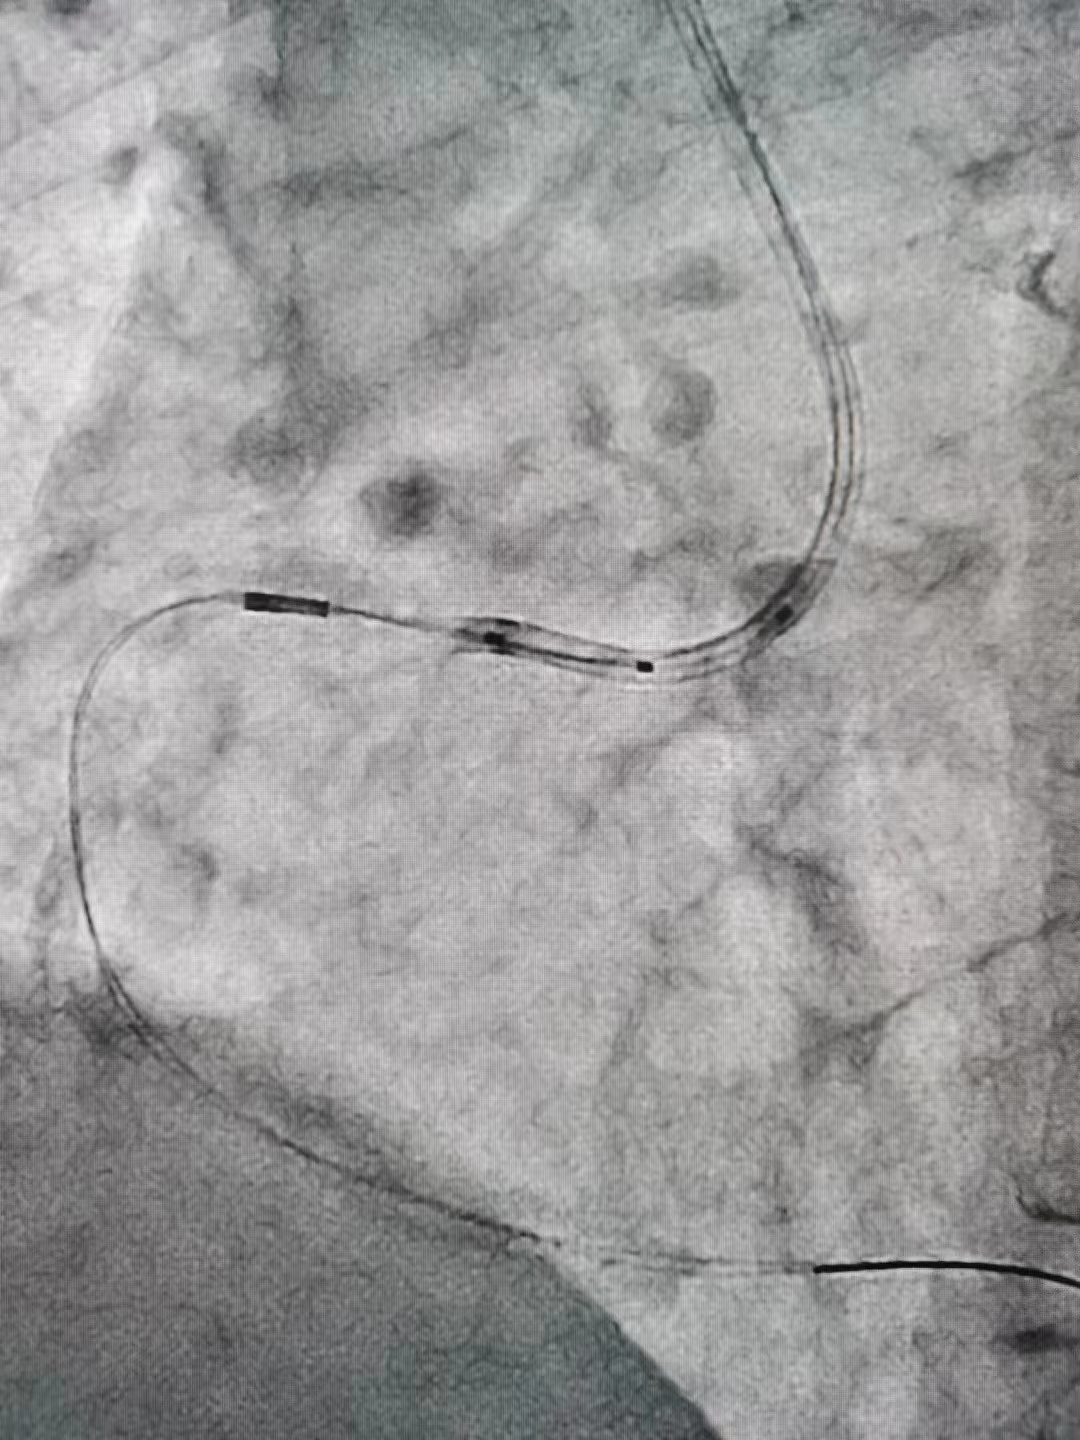

冠脉内介入治疗